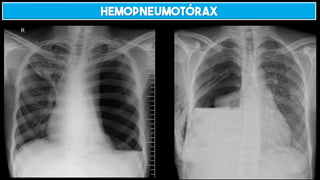

HEMOPNEUMOTÓRAX